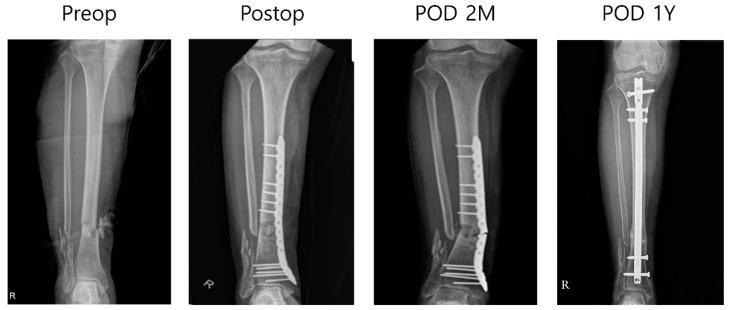

Distal tibia fractures are high-energy injuries characterized by a mismatch between standard plate designs and the patient's specific anatomical bone structure, which can lead to severe soft tissue damage. Recent advancements have focused on the development of customized metal plates using three-dimensional (3D) printing technology. However, 3D-printed metal plates using titanium alloys have not incorporated a locking system due to the brittleness of these alloys. Therefore, this study aimed to determine whether a locking mechanism can be effectively implemented using 3D-printed pure titanium and further evaluate the clinical outcomes of such implants in patients with distal tibia fractures. : Between March 2021 and June 2022, nine patients who underwent open reduction and internal fixation for distal tibia fractures using 3D-printed pure titanium plates were enrolled. Pure titanium powder (Ti Gr.2, Type A, 3D Systems, USA) was spread to a thickness of 30 μm and partially sintered using a 500 W laser to produce the 3D-printed metal plates. The locking screws were fabricated using a milling process. Open reduction and internal fixation were performed on the nine patients using 10 customized plates. The clinical efficacy was analyzed using the union rate, and complications, such as infection and skin irritation, were evaluated to ensure a comprehensive outcome assessment. Surgical treatment was successfully performed on nine patients, with nine of ten plates remaining stable and undamaged. However, one patient with neurofibromatosis experienced a fractured metal plate, which necessitated revision surgery using a metal rod. No screw loosening or surgical wound complications occurred. This study showed that 3D-printed pure titanium plates with integrated locking screw systems provide a viable and effective solution for managing distal tibia fractures. Three-dimensional printing and pure titanium show promise for orthopedic advancements.

胫骨远端骨折是高能损伤,其特点是标准钢板设计与患者特定的解剖骨骼结构不匹配,这可能导致严重的软组织损伤。最近的进展集中在使用三维(3D)打印技术开发定制金属板。然而,由于钛合金的脆性,使用钛合金的3D打印金属板尚未纳入锁定系统。因此,本研究旨在确定是否可以使用3D打印的纯钛有效地实现锁定机制,并进一步评估此类植入物在胫骨远端骨折患者中的临床结果。2021年3月至2022年6月,招募了9例使用3D打印纯钛板进行胫骨远端骨折切开复位内固定的患者。将纯钛粉末(Ti Gr.2,A型,3D Systems,美国)铺展至30μm的厚度,并使用500W激光进行部分烧结以生产3D打印金属板。锁定螺钉采用铣削工艺制造。使用10块定制板对9例患者进行了切开复位内固定。使用愈合率分析临床疗效,并评估感染和皮肤刺激等并发症,以确保进行全面的结果评估。9例患者手术治疗成功,10块板中有9块保持稳定且未受损。然而,1例患有神经纤维瘤病的患者金属板发生骨折,需要使用金属棒进行翻修手术。未发生螺钉松动或手术伤口并发症。本研究表明,具有集成锁定螺钉系统的3D打印纯钛板为治疗胫骨远端骨折提供了一种可行且有效的解决方案。三维打印和纯钛在骨科进展方面显示出前景。